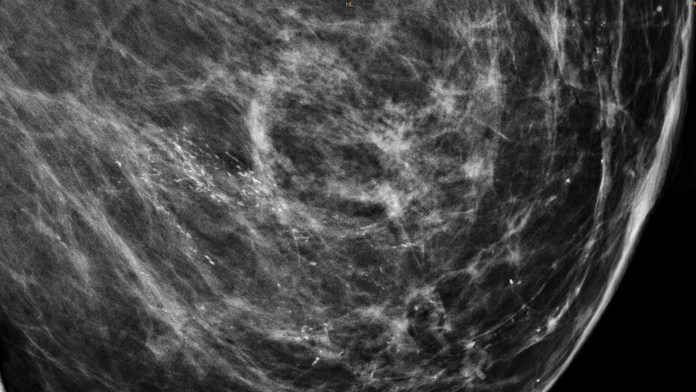

Mikrokalk ist nicht automatisch besorgniserregend. Fachleute gehen aber davon aus, dass etwa 3 bis 4 von 10 bösartigen Brusttumoren solche Kalkeinlagerungen aufweisen. Daher kann Mikrokalk auf Brustkrebs hinweisen – vor allem wenn er auf bestimmte Weise geformt oder verteilt ist.

Mikrokalk in der Mammographie untersuchen Ärztinnen und Ärzte daher genau, um eindeutig gutartige Befunde von verdächtigen Mikroverkalkungen abzugrenzen. Möglicherweise sind dafür weitere Mammographie-Aufnahmen und/oder eine Gewebeprobe (Biopsie) nötig. Wenn sich Mikroverkalkungen jedoch über mehrere Jahre nicht verändern, gehen Fachleute üblicherweise davon aus, dass sie harmlos sind.

Auch sogenannte in-situ-Tumoren weisen häufig Mikroverkalkungen auf. Solche Tumoren können sich zu einem invasiven Brustkrebs entwickeln, der zerstörend in umliegendes Gewebe wächst. Deshalb sollte auffälliger Mikrokalk in der Mammographie immer abgeklärt werden.

Gut zu wissen: Deodorants, Puder und Cremes auf der Haut können in den Röntgenbildern der Mammographie wie Mikrokalk aussehen. Erfahrene Ärztinnen und Ärzte erkennen diese sogenannten Artefakte oder auch Pseudomikrokalk in der Regel schnell, dennoch empfiehlt es sich, am Tag einer Mammographie auf Deo, Puder und Cremes zu verzichten.

Bildhinweis: Das Copyright des Bildes "Mikrokalk erscheint in Mammographie-Aufnahmen intensiv weiß." liegt bei Jmarchn, Wikimedia Commons (CC BY 3.0).